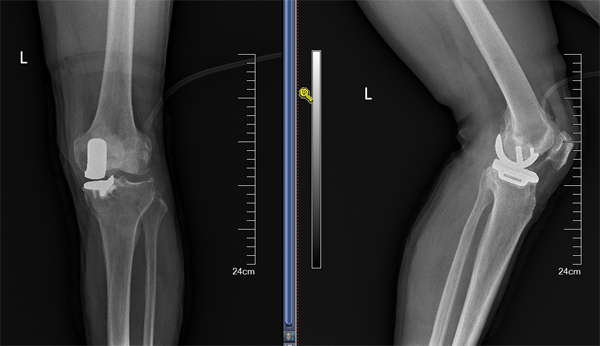

膝关节单髁手术技术从零到有

王伟教授入住骨科后,定期对关节组医师进行授课及专业培训,充分评估患者病情,严格掌握手术适应症,仔细规划术前方案,指导洛阳市中心医院骨科顺利开展膝关节单髁置换手术,实现了该院膝关节单髁置换技术零的突破。目前,该院骨科已能常规开展该技术,促进了洛阳市中心医院关节技术的发展。单髁置换手术是虽然是较为传统的膝关节终末期关节炎的治疗手段之一,早期由于各种原因导致这种优良的手术方式与全膝关节置换术比较发展较为缓慢,但随着近年置换适应症把握、关节假体设计及关节材料的进步多种原因,使单髁置换术成优良的微创保膝治疗手段,在国内外得到广泛的推广。单髁置换术应用于合适的终末期骨关节炎患者后,相比全膝关节置换具有,创伤小,恢复快,病人满意度高等优势,同样得到广大的患者的认可和首选。由于单髁置换讲究更高的置换精度,要求精细,而准确的手术操作,对手术医师的素养具有更高要求,只有具有一定手术量积累的医生,才能获得良好效果,减低手术风险。洛阳中心医院单髁置换手术方式的开展,代表在保膝,微创治疗中迈上一个新台阶。